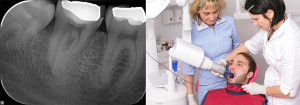

Z lokalnim rentgenskim slikanjem dobimo posnetek izbranega zoba, dela zoba, lahko pa tudi dveh sosednjih zob. Lokalno slikanje nudi koristne informacije pri endodontskem zdravljenju, pri izdelavi zatiča, pri poškodbah, za oceno izgube kosti pri parodontalni bolezni, pri ekstrakcijah, apikotomiji, implantatih in drugih zobozdravstvenih posegih.